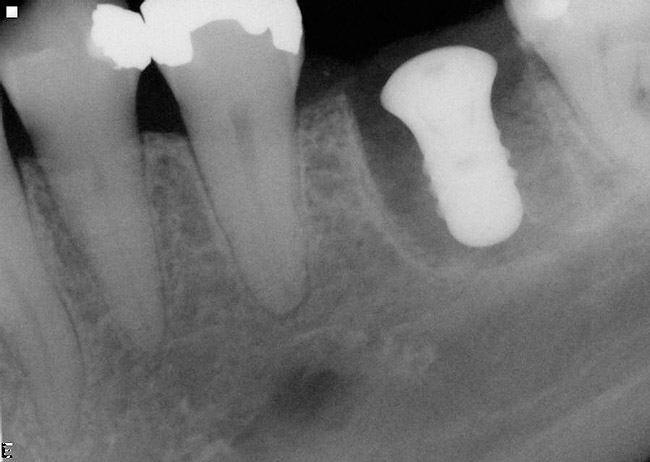

Figure 11  The mandibular first molar was fractured. Note the periapical lesions around this tooth.

Figure 11

Figure 12  After the first molar was extracted and hemisected without damaging the interradicular bone, an initial osteotomy was prepared in the interradicular bone utilizing a 2.2-mm-wide bur.

Figure 12

Figure 13  A radiograph of a guide pin in the prepared osteotomy.

Figure 13

Figure 14  An implant with a 4.8-mm-wide body and a 6.5-mm-wide restorative platform was placed in the interradicular bone following appropriate preparation.

Figure 14